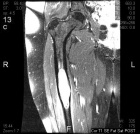

40 year old female with history of pain in low back and right thigh pain for the past eighteen months

Zoom image: Radiological image Radiological image.